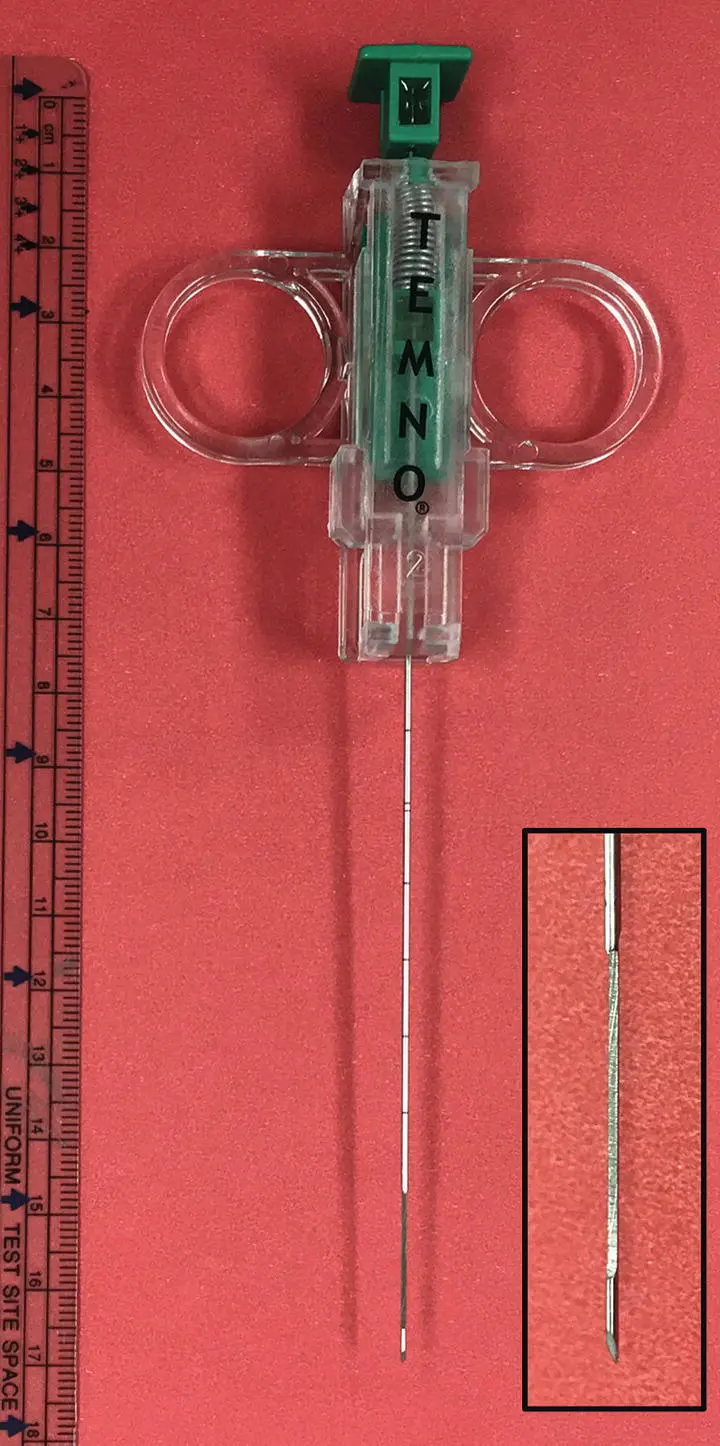

Figure 2.24 Ultrasound guidance is used to obtain a lung biopsy using a Temno biopsy needle.

Percutaneous lung biopsy can be obtained with use of an ultrasound‐guided biopsy needle in the anesthetized patient. This is performed more commonly in dogs than in cats. A surgical preparation is performed, and a 16–18 gauge Temno™ biopsy needle (Merit Medical Systems, South Jordan, UT) is guided into the lesion to obtain a 2 cm core tissue sample for histopathology ( Figure 2.24). After either aspiration or biopsy, the animal should be placed in lateral recumbency with the side of the aspiration facing downward for 15–30 minutes to promote the development of a clot or seal at the aspiration site. Typically, an ultrasound is performed after the procedure to screen for hemorrhage or pneumothorax. Visualization of the normal “glide” sign as the lung slides across the pleura rules out one of these complications. An increase in respiratory rate or effort or detection of absent lung sounds near the site of aspiration would indicate hemorrhage or pneumothorax and the need for intervention.